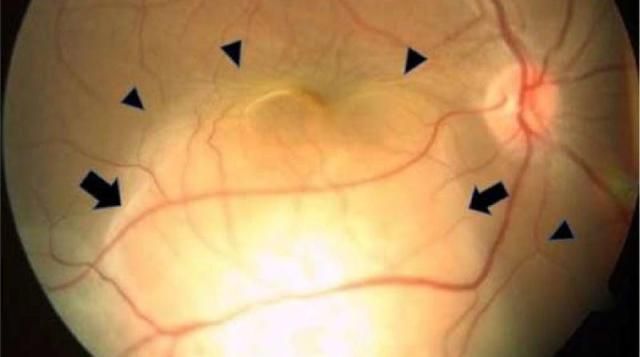

وقد كشفت التقييمات الأوّلية في المستشفى عن هياكل عينية طبيعية ظاهريًّا، خالية من الألم أو الاحمرار، لكن الفحص الدقيق كشف عن وجود كتلة كبيرة بيضاء مائلة إلى الصفرة في الجزء الخلفي من عينها اليمنى، مصحوبة بتراكم السوائل تحت الشبكية؛ ما أدى إلى انفصالها. كما تم اكتشاف آفة أصغر في عينها اليسرى، وإن كانت شبكية العين سليمة.

صورة للعين تظهر الآفة السرطانية وانفصال الشبكيةElsevier